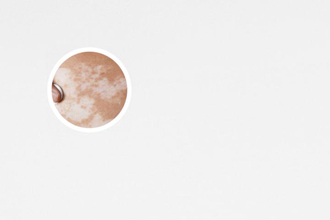

我們需要明確一點(diǎn):白點(diǎn)癲風(fēng)不是白癜風(fēng)疾病。白點(diǎn)癲風(fēng)是指皮膚上出現(xiàn)的白色斑點(diǎn),通常是由于皮膚內(nèi)的色素沉著不均勻所致。而白癜風(fēng)則是一種自身免疫性疾病,與遺傳因素有關(guān)。所以,在回答白點(diǎn)癲風(fēng)是否會(huì)遺傳給下一代的問題時(shí),我們需要明確疾病的范疇。

根據(jù)目前的調(diào)查和醫(yī)學(xué)觀察,白點(diǎn)癲風(fēng)并不是一種遺傳疾病。多數(shù)情況下,白點(diǎn)癲風(fēng)是由于外界刺激、長(zhǎng)期緊張、免疫功能失調(diào)等因素引起的。而且,白點(diǎn)癲風(fēng)與個(gè)體的生活方式、環(huán)境因素等也有一些關(guān)系。因此,它不會(huì)直接遺傳給子女。